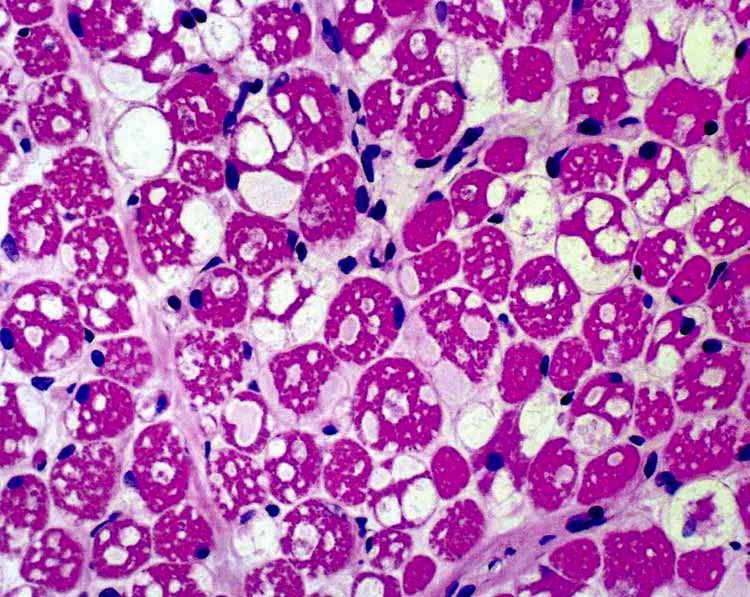

Pompe Disease - severe vacuolar myopathy due to extensive glycogen storage